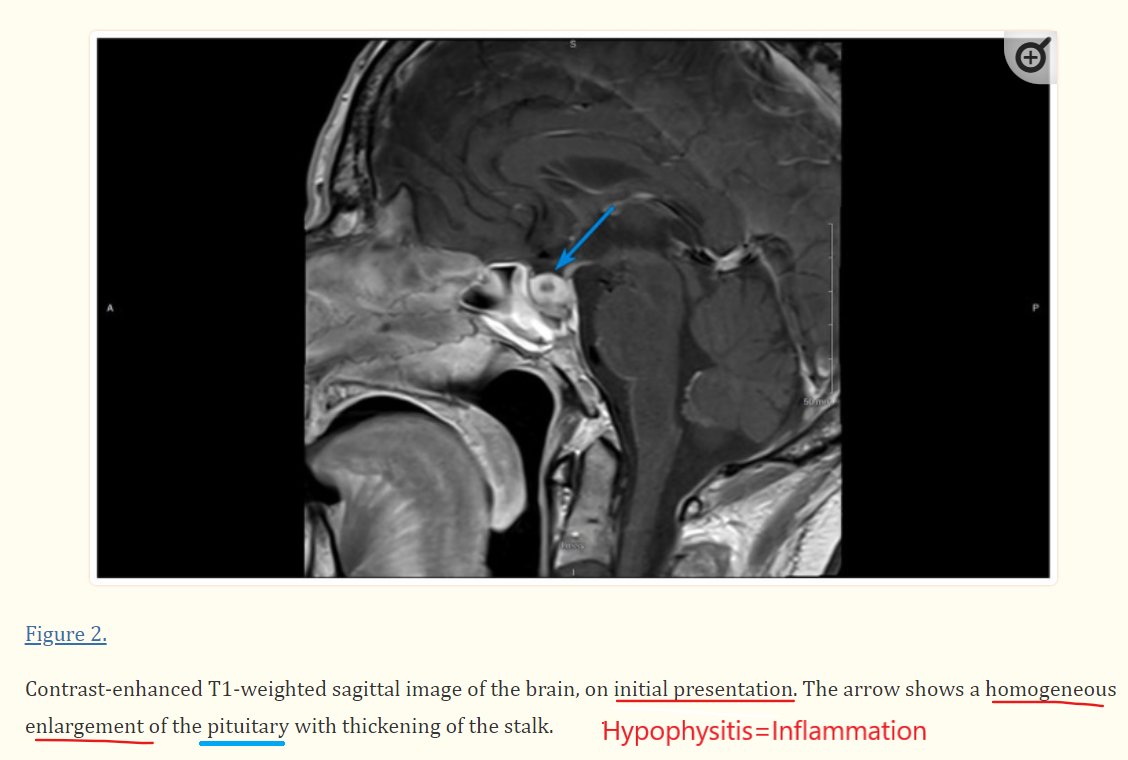

Des troubles hormonaux sont-ils possibles après l’Cov19 ? Réponse Destruction auto-immune avec fusion et perte complète d'un organe de contrôle central - la glande pituitaire - est décrite dans les études suivantes https://ncbi.nlm.nih.gov/pmc/articles/PMC8474296/ https://elsevier.es/en-revista-clinics-22-articulo-the-pituitary-gland-in-sars-cov-2-S1807593222033580

A Case of Hypophysitis Following Immunization With the mRNA-1273 SARS-CoV-2 Vaccine The emergence of a novel coronavirus and global pandemic raised the need for the rapid development of new vaccines to reduce the morbidity and mortality associated with Covid-19. Common side effects of these vaccines such as myalgia, arthralgia, nausea, fatigue, ... ncbi.nlm.nih.gov

The pituitary gland in SARS-CoV-2 infections, vaccinations, and post-COVID syndrome | Clinics IntroductionThere is ample evidence that SARS-CoV-2 not only affects the lungs but all other organs as well, particularly the Central Nervous elsevier.es

@AnteMedicus - Medicus Ante

#mRNA #vaccine Are hormone disorders possible following the C19 gene treatment? Autoimmune destruction with meltdown and the complete loss of a central control organ - the pituitary gland is described in the following studies: https://www.ncbi.nlm.nih.gov/pmc/articles/PMC8474296/ https://www.elsevier.es/en-revista-clinics-22-articulo-the-pituitary-gland-in-sars-cov-2-S1807593222033580